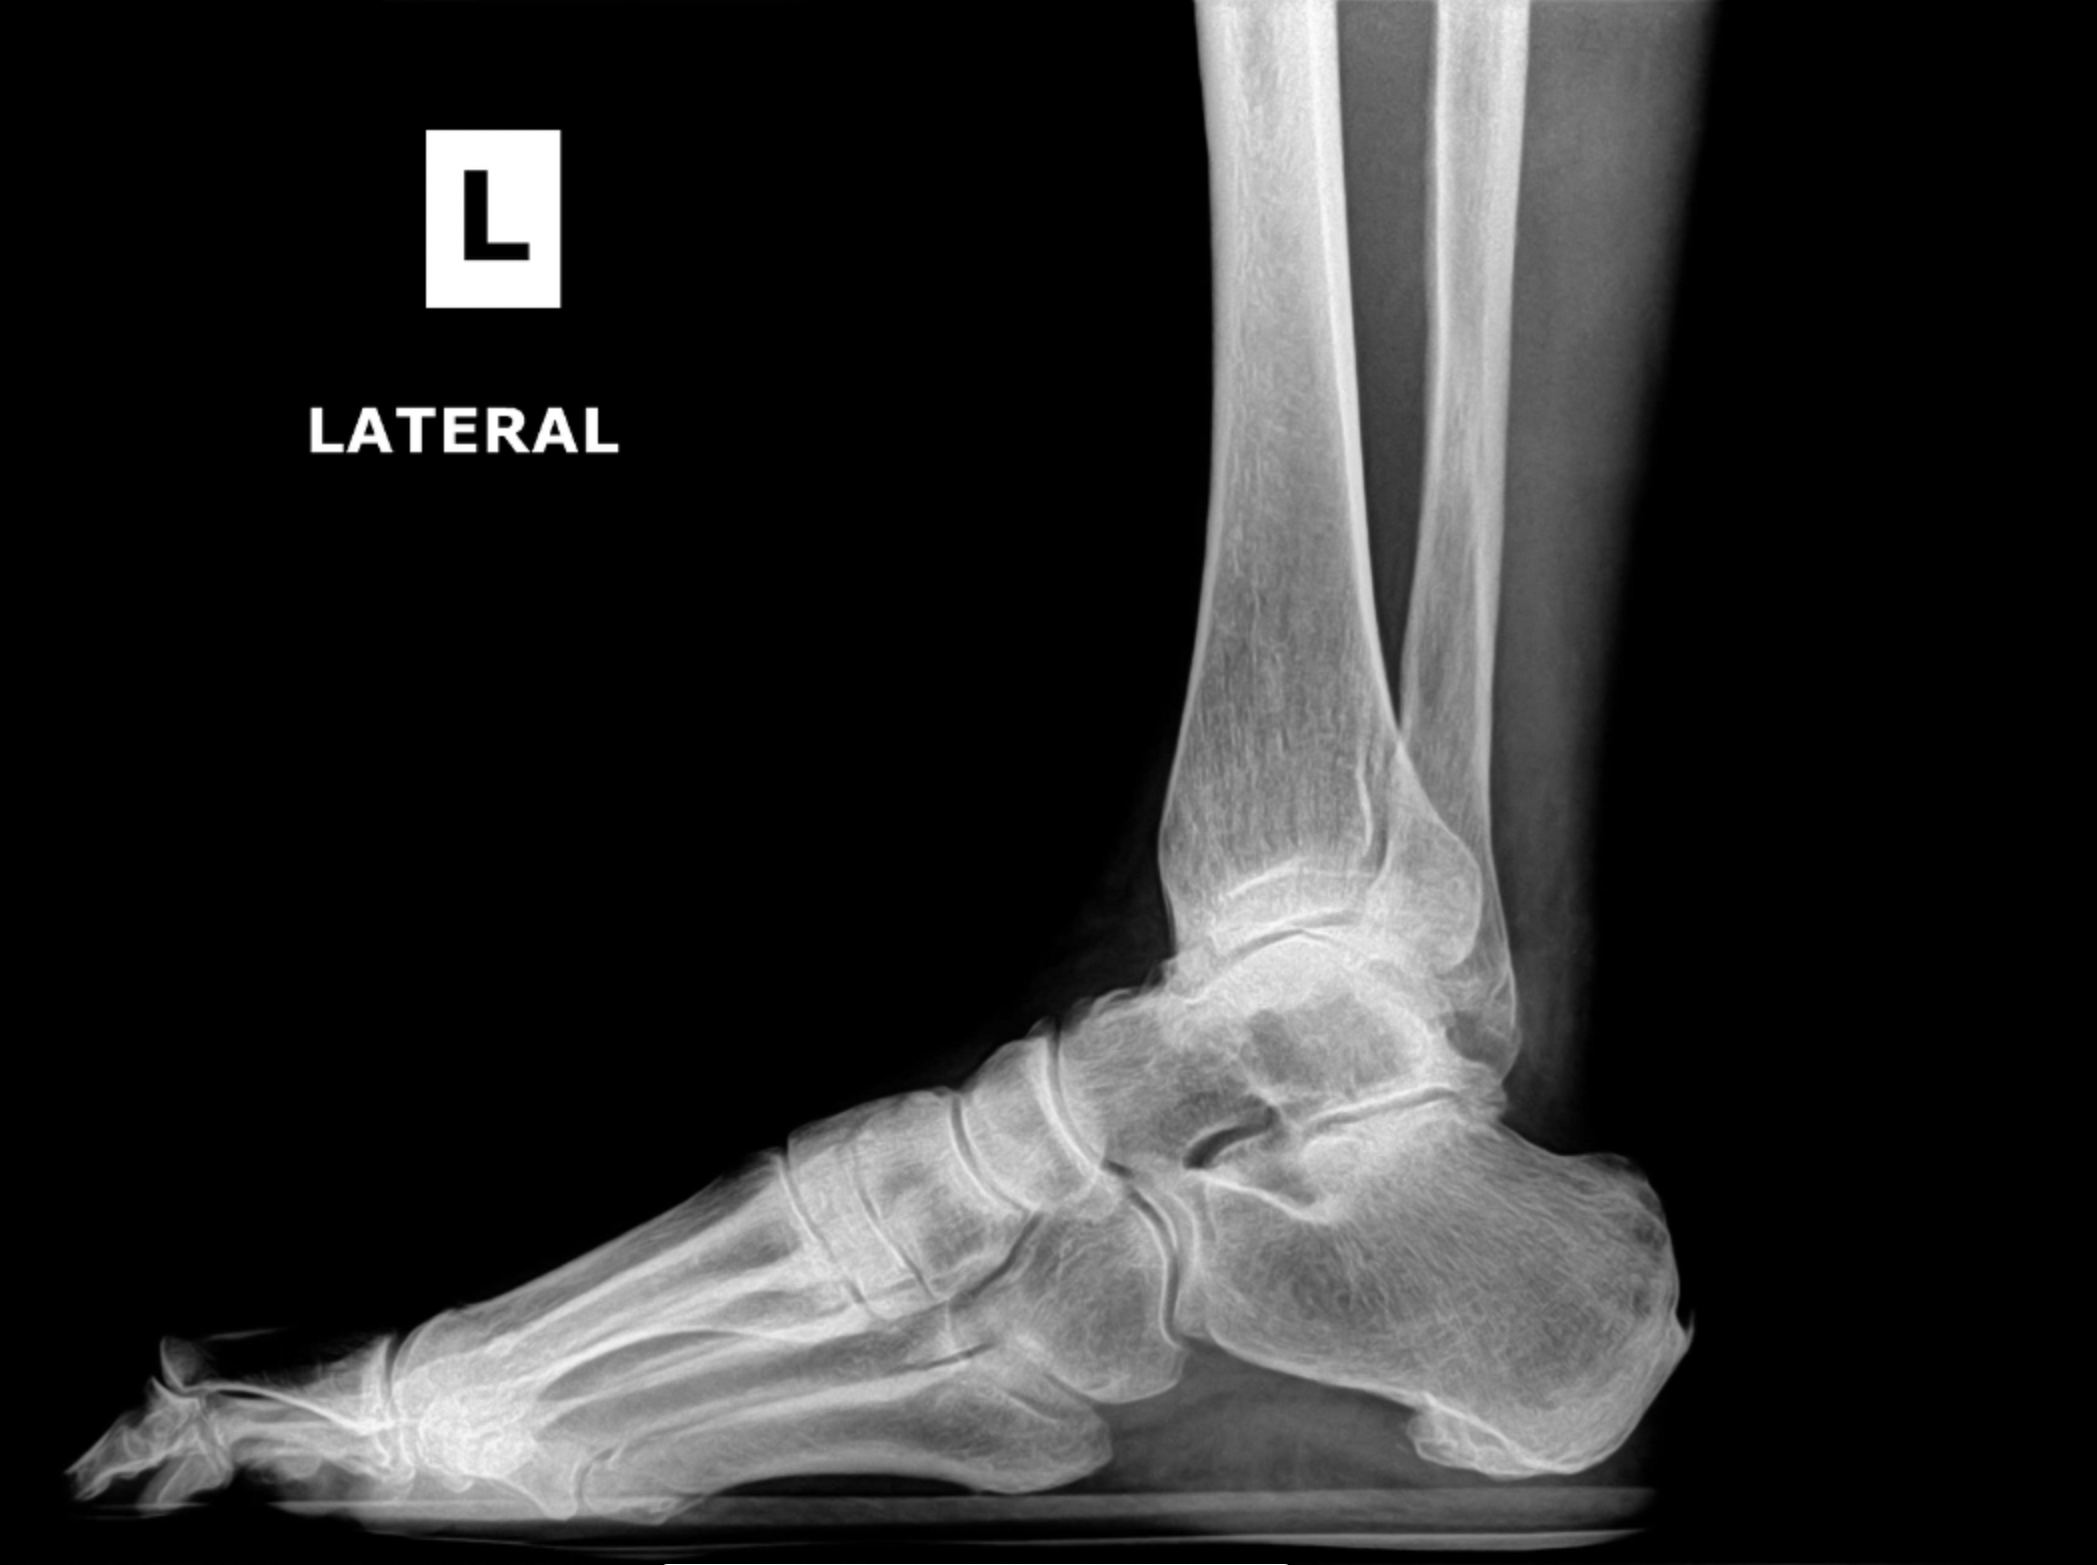

Foot & Ankle Replacement